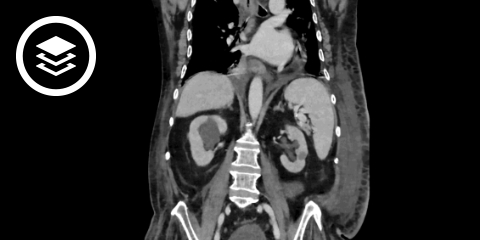

CT-Fallbeispiele

Bildquelle

- Bildquelle DICOM-Viewer Harnstau: Datensatz freundlicherweise zur Verfügung gestellt durch die Klinik für diagnostische und interventionelle Radiologie, St. Vinzenz Hospital Köln